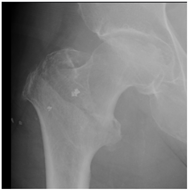

For X-ray 4, four scenarios were developed.![]() | Scenario 1: What would be your operation preference for a mobile patient aged 50–70 and with an ASA score of 1–2? Scenario 2: What would be your operation preference for a mobile patient aged 71 years or older with an ASA score of 1–2? Scenario 3: What would be your operation preference for a mobile patient aged 50–70 with an ASA score of 3–4? Scenario 4: What would be your operation preference for a mobile patient aged 71 years or older with an ASA score of 3–4? |